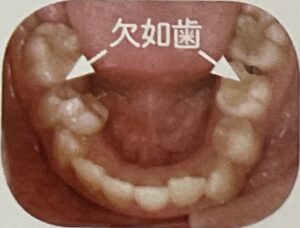

例えば、お口がポカンと開いている子は出っ歯になりやすかったり、舌も本来の正しい位置から下がってしまっている状態なので上顎がしっかり成長せず歯がガタガタになりやすいと言われています。